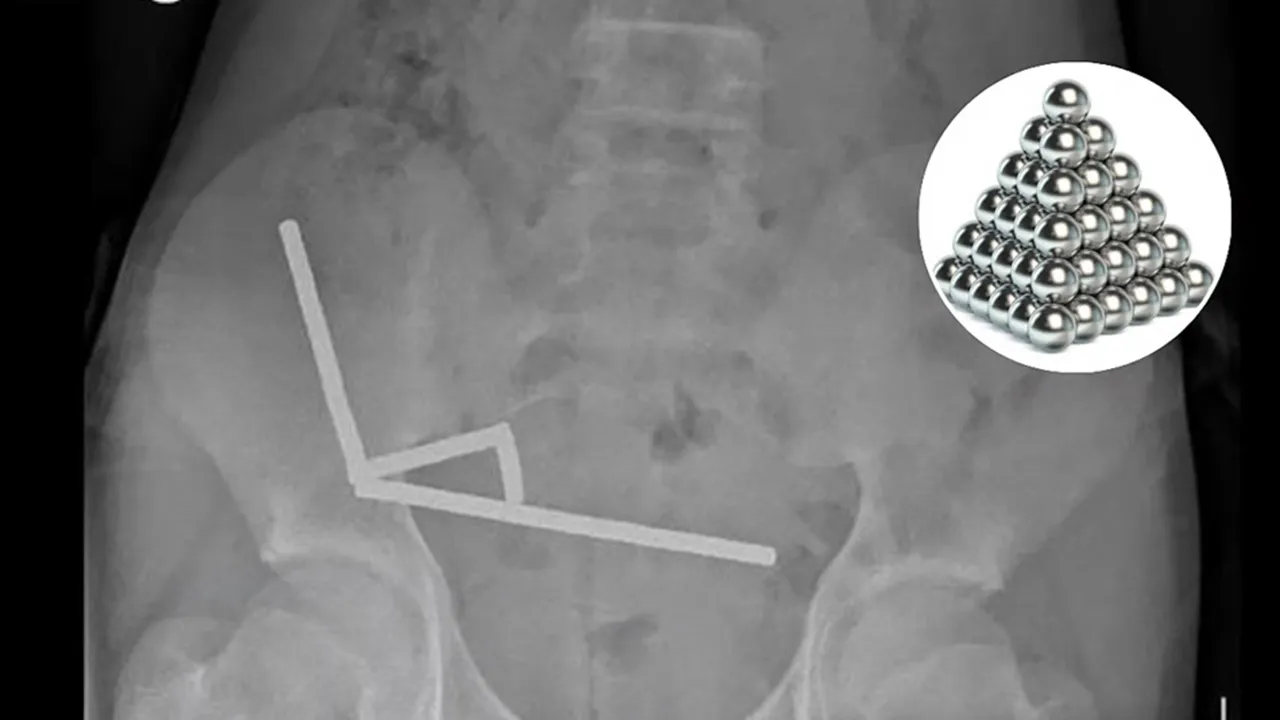

ವೆಲ್ಲಿಂಗ್ಟನ್: 13 ವರ್ಷದ ಬಾಲಕನೊಬ್ಬ ಇಂಟರ್ನೆಟ್ನಲ್ಲಿ ಇ-ಕಾಮರ್ಸ್ ಮಾರುಕಟ್ಟೆಯಿಂದ ಹೈ-ಪವರ್ ಅಯಸ್ಕಾಂತಗಳನ್ನು ಖರೀದಿಸಿ ನುಂಗಿರುವ ಆಘಾತಕಾರಿ ಘಟನೆ ನ್ಯೂಜಿಲ್ಯಾಂಡ್ನಲ್ಲಿ (New Zealand) ನಡೆದಿದೆ. 100 ಕ್ಕೂ ಹೆಚ್ಚು ಅಯಸ್ಕಾಂತಗಳನ್ನು (Magnets) ನುಂಗಿದ ನಂತರ ಬಾಲಕ ಶಸ್ತ್ರಚಿಕಿತ್ಸೆಗೆ ಒಳಗಾಗಬೇಕಾಯಿತು. ಈ ವೇಳೆ ವೈದ್ಯರು ಅವನ ಕರುಳಿನ ಒಂದು ಭಾಗವನ್ನು ತೆಗೆದುಹಾಕಬೇಕಾಯಿತು. ಈ ಸುದ್ದಿ ಇದೀಗ ವೈರಲ್ (Viral News) ಆಗಿದೆ.

2014 ರಿಂದ ದೇಶೀಯ ಅಥವಾ ವೈಯಕ್ತಿಕ ಬಳಕೆಗಾಗಿ ಸಣ್ಣ, ಹೈ-ಪವರ್ ಅಯಸ್ಕಾಂತಗಳ ಮಾರಾಟವನ್ನು ನ್ಯೂಜಿಲ್ಯಾಂಡ್ ನಿಷೇಧಿಸಿದ ನಂತರವೂ ಈ ಆತಂಕಕಾರಿ ಘಟನೆ ಸಂಭವಿಸಿದೆ. ಜನಪ್ರಿಯ ಆನ್ಲೈನ್ ಮಾರುಕಟ್ಟೆಯಾದ ಟೆಮುನಿಂದ ಆರ್ಡರ್ ಮಾಡಿದ್ದ 100ಕ್ಕೂ ಹೆಚ್ಚು ಆಯಸ್ಕಾಂತಗಳನ್ನು ಬಾಲಕ ನುಂಗಿದ್ದ. ಶಸ್ತ್ರಚಿಕಿತ್ಸೆಗೆ ಒಂದು ವಾರದ ಮೊದಲು ಆ ಹದಿಹರೆಯದ ಬಾಲಕ ಸುಮಾರು 80 ರಿಂದ 100 ಸಣ್ಣ ಆಯಸ್ಕಾಂತಗಳನ್ನು ನುಂಗಿದ್ದ ಎಂದು ಟೌರಂಗಾ ಆಸ್ಪತ್ರೆಯ ಶಸ್ತ್ರಚಿಕಿತ್ಸಕರು ತಿಳಿಸಿದಿದ್ದಾರೆ. ಅವೆಲ್ಲವನ್ನೂ ಬಾಲಕ ಆನ್ಲೈನ್ ಮಾರುಕ್ಟಟೆಯಾದ ಟೆಮುವಿನಲ್ಲಿ ಖರೀದಿಸಿದ್ದನು.

ನಾಲ್ಕು ದಿನಗಳ ಕಾಲ ಸಾಮಾನ್ಯ ಹೊಟ್ಟೆನೋವಿನಿಂದ ಆಸ್ಪತ್ರೆಗೆ ದಾಖಲಾದ 13 ವರ್ಷದ ಬಾಲಕನ ಪ್ರಕರಣವನ್ನು ನಾವು ಪರಿಶೀಲಿಸುತ್ತಿದ್ದೇವೆ ಎಂದು ವೈದ್ಯರ ತಂಡ ಹೇಳಿತ್ತು. ಬಾಲಕ ಸುಮಾರು ಒಂದು ವಾರದ ಹಿಂದೆ ಸುಮಾರು 80–100 5x2mm ಹೈ-ಪವರ್ (ನಿಯೋಡೈಮಿಯಮ್) ಆಯಸ್ಕಾಂತಗಳನ್ನು ಸೇವಿಸಿದ್ದಾಗಿ ಬಹಿರಂಗಪಡಿಸಿದ್ದಾನೆ. ಇವುಗಳನ್ನು ವಿದೇಶಿ ಆನ್ಲೈನ್ ಮಾರುಕಟ್ಟೆಯಿಂದ (ಟೆಮು) ಖರೀದಿಸಲಾಗಿತ್ತು.